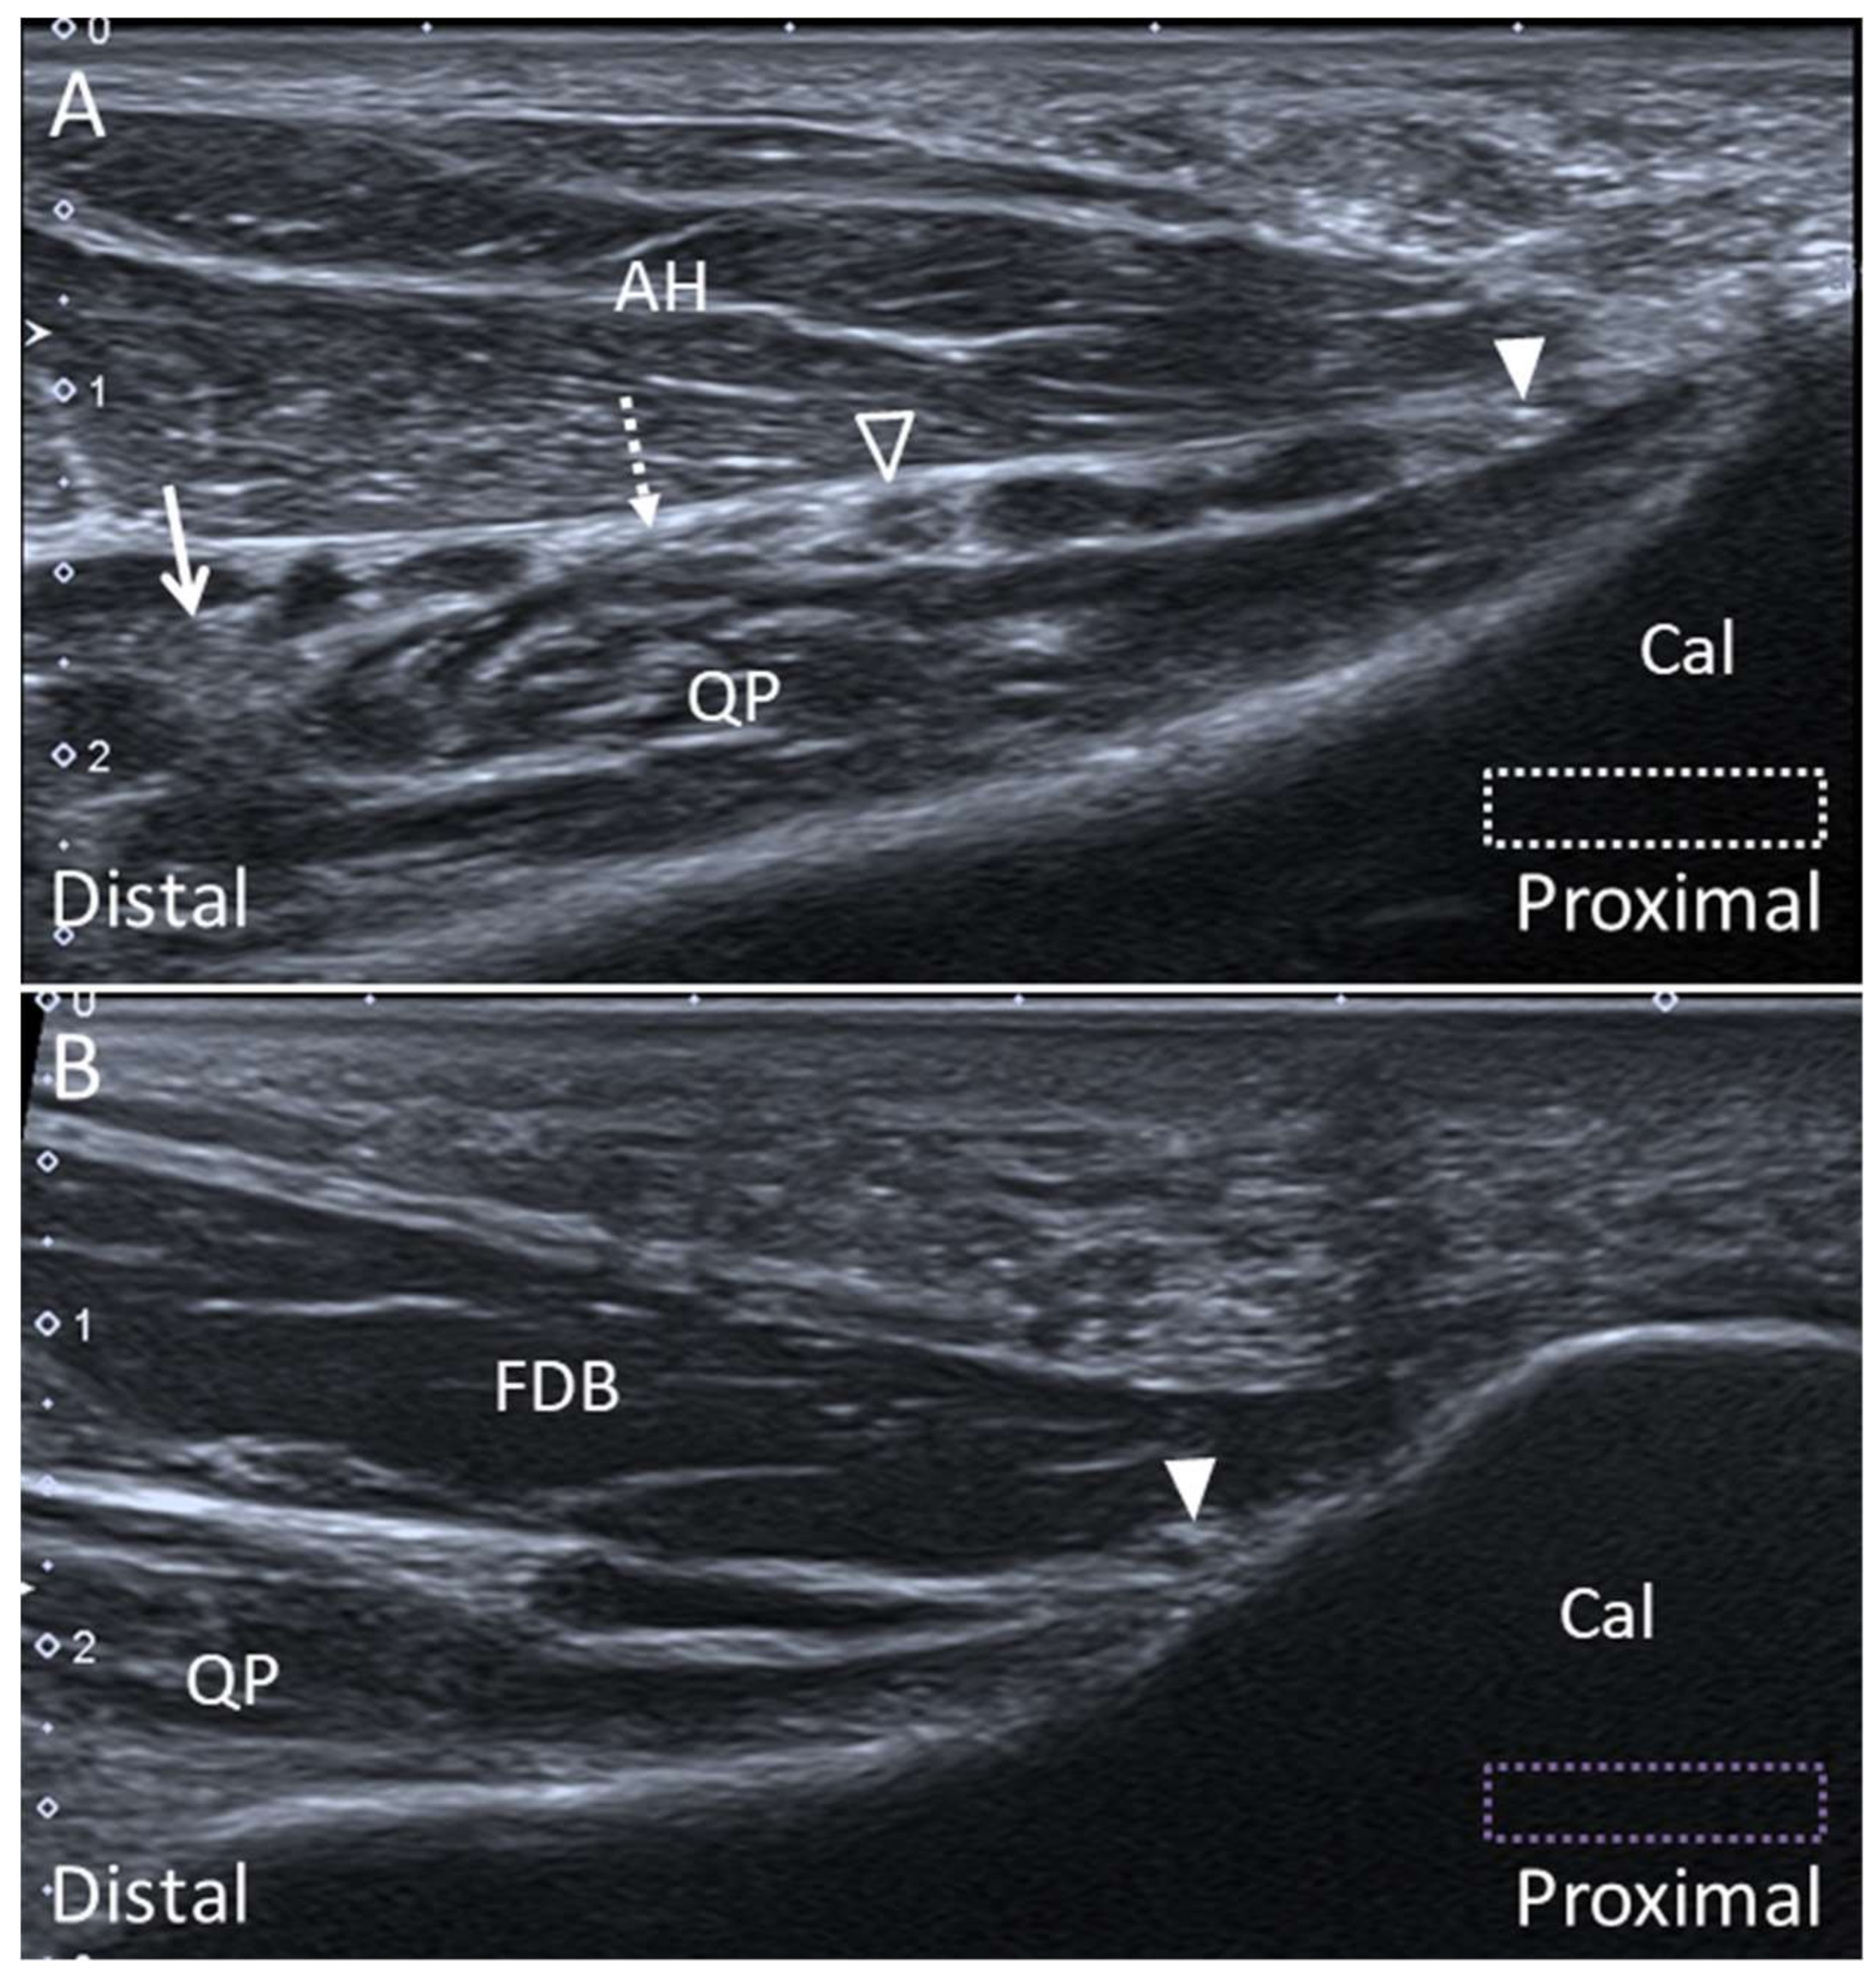

5.2. Baxter Nerve

5.2.1. Anatomy

5.2.2. Scanning Technique

5.2.3. Clinical Relevance